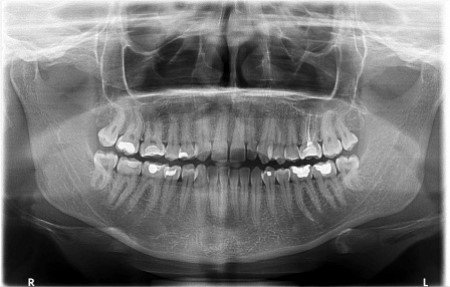

• panoraminę radiogramą (1 pav.) – vertinamas dantų santykis su žandinio ančio dugnu, pneumatizacija ir pseudocistos, šaknų, dantų pasislinkimas ar svetimkūniai antyje;

1 pav. Panoraminė radiograma (10)

Kartais, kai yra pašalintas uždegimą sukėlęs dantis ir įtariama, kad žandinis antis susijungia su burnos ertme, radiologinis tyrimas atliekamas su gutaperčios kaiščiu alveolėje (3). Uždegimui esant odontogeninės kilmės, ligą sukėlusio danties vainike bus stebimas danties ėduonis ar užpildas arti pulpos kameros. Stebimi ir periodonto radiologiniai pakitimai – padidėjęs ir išplatėjęs periodonto plyšys su kaulo destrukcija (3). Kartais antyje gali būti randama plombinės medžiagos ar lūžusių endodontinių instrumentų (2–4, 6). Pašalinus OŽS sukėlį dantį, žandiniam ančiui jungiantis su burnos ertme, matoma šio danties alveolė, nepripildyta kaulo, ir nevientisas, suardytas, su defektu žandinio ančio apatinės sienos radiologinis vaizdas. Atliktos žandinio ančio radiogramos yra lyginamos – dešinė yra lyginama su kaire (2). Radiologiniuose vaizduose stebimas gleivinės paburkimas, kuris gali būti lokalus, dėl pūlingo uždegimo matoma vadinamoji skysčio linija (3 pav.), užtemęs sinusas (2–4, 9).